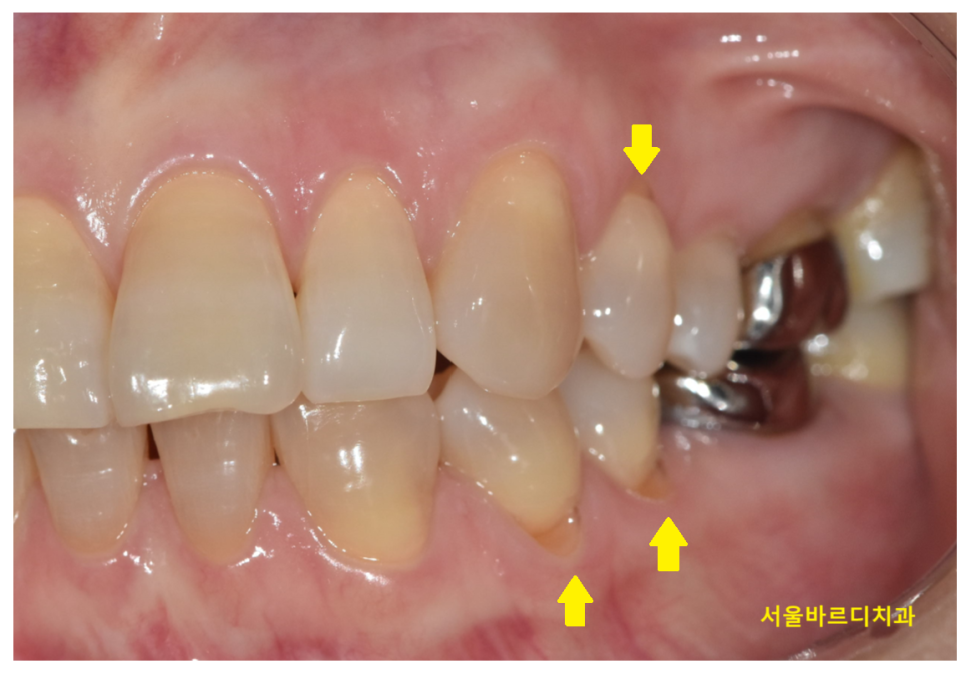

첫번째로 잇몸뼈가 내려갔다거나

치아 뿌리가 노출됐다거나 하는 이유가 있어요!

치아 뿌리가 패이게 되면 치아 신경과 가깝게되고

상아질이라는 구조가 드러나게 되어

외부 자극 (찬물, 신 음식 등) 에 민감하게 반응하게 됩니다.